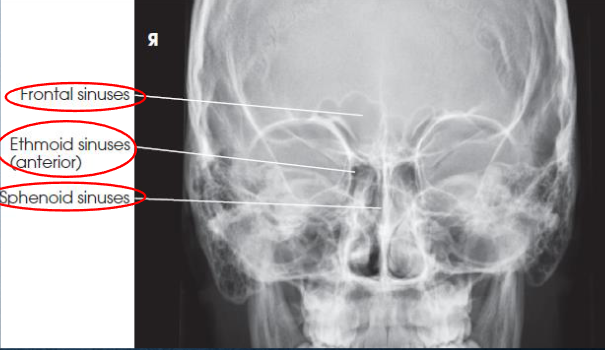

PA axial (Caldwell) sinuses

patient position:

upright

MSP centered to midline

part position, angled grid technique:

tilt vertical Bucky down 15 degrees (horizontal CR)

rest forehead and nose on IR

center nasion to IR

MSP and OML perpendicular to IR

part position, vertical grid technique:

extend neck to rest tip of nose on Bucky

OML 15 degrees to horizontal IR

sponge can be used to support forehead

center nasion to IR

MSP perpendicular to IR

not preferred because of an increased OID, which results in decreased resolution

respiration suspended

CR:

horizontal, exits nasion

15 degree relationship between CR and OML

collimation:

1 inch beyond the lateral skin shadows, superiorly to include just the shadow of the top of the head, and inferiorly to the occlusal plane

PA axial (Caldwell) sinuses image criteria

demonstrates:

frontal sinuses above frontonasal suture

anterior ethmoidal air cells

sphenoid sinuses seen through nasal fossa below or between ethmoids

petrous pyramodis lower third of orbits

primarily demonstrates the frontal sinuses and anterior ethmoidal air cells

anterior ethmoidal air cells above petrous ridges

no rotation or tilt

equidistant lateral borders of the skull and lateral borders of the orbits

symmetric petrous ridges

MSP of head aligned with long axis of collimated field

air-fluid levels, if present